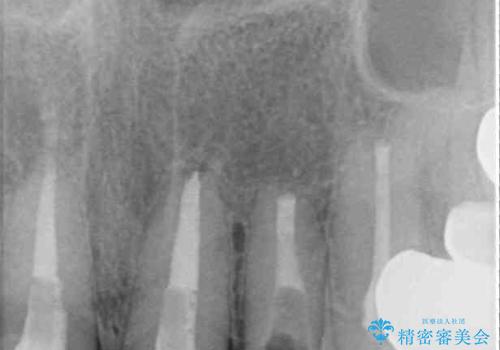

- 前歯が土台ごと外れてしまったとのことで来院された患者様です。

土台は外れていましたが破折などの問題はなく、土台からの再治療で対応可能な状態でした。

隣の犬歯も神経が取り除かれていたしたが、ラミネートベニアで治療されており、裏側でむし歯が進行する可能性があったため、こちらも治療が必要と判断されました。